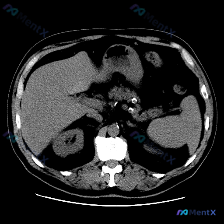

整理了一个很有警示意义的读片场景,大家可以一起看看思路有没有问题。 --- 核心情况 用户给了一张上腹部CT增强横断面(初步判断为动脉期/动静脉混合期),预设问题是“图像中的特定异常是什么?脾脏病变”。 影像事实(关键) 拿到图像分析结果先看客观描述: 1. 图像质量:良好,无明显呼吸/运动伪影,软...